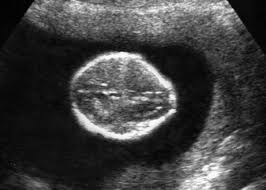

Here are common soft markers that show up in the second-trimester ultrasound. Mid-trimester soft markers have been linked with Down syndrome and other aneuploidies. Thickened nuchal fold echogenic bowel shortened femur shortened humerus pyelectasis and absent or hypoplastic nasal bone.

Ultrasound is a key component of aneuploidy screening. Ultrasonically echoreflective bowel bright gut short femurs clinodactyly of the fifth digit and oddly shaped heads have all been identified as soft markers associated with an increased risk of trisomy. Soft markersDown syndrome.

Certain features detected during a second trimester ultrasound exam are potential markers for Downs syndrome and they include dilated brain ventricles absent or small nose bone increased. But there is nothing to worry about and my child is perfectly normal Becauese my first-trimester scan and blood test were both normalBUT I need to make an appointment with a genetic. Approximately 30 of babies with Down syndrome have detectable abnormalities on the mid-trimester ultrasound 1.

There are specific characteristics identified during an ultrasound exam in the second trimester of a womans pregnancy that are possible indicators for Downs syndrome. Both major structural abnormalities and minor soft markers can be detected by ultrasound in fetuses affected with aneuploidies. There are many other prenatal screening tests available with better detection rates for Down syndrome than the mid-trimester ultrasound.